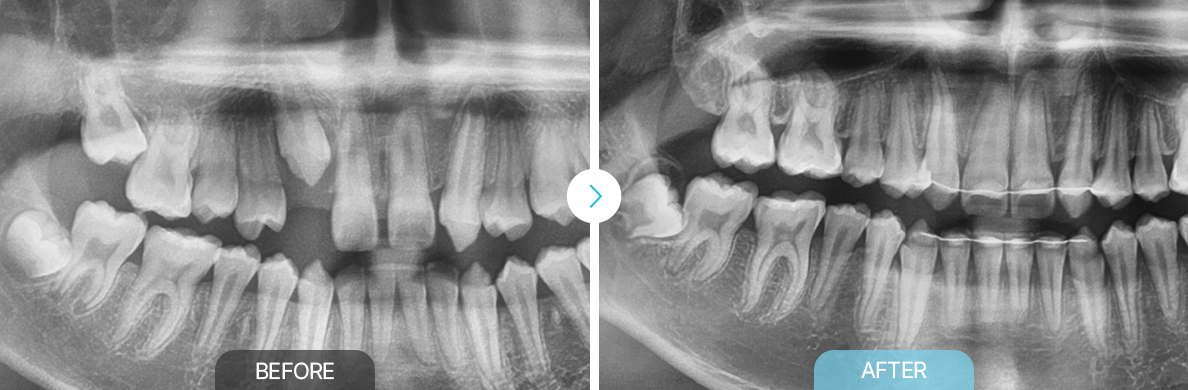

맹출유도교정

부천상동 맹출유도교정, 부천치과, 맹출유도교정 상동 맹출유도교정 부천연세퍼스트치과, 교정치과 부천상동, 맹출유도교정 부천교정치과